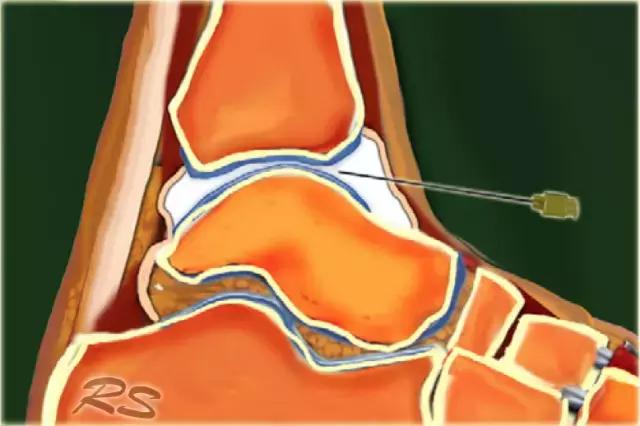

胫骨关节 CT或MR关节镜可用于查询韧带,骨软骨或软骨损伤,评价自由体或查询骨软骨病变的稳定性。对于踝关节(胫骨关节)的注射,患者仰卧,足部轻微的跖屈。用超声波检查胫骨关节的内侧,以确定合适的注射部位,同时检查任何过量的关节液。我们使用小型弯曲阵列8 MHz传感器,但如果优选,可以使用18-12 MHz线性阵列传感器。 探头的长轴保持在矢状面内。

通常为22号(长度:30mm)的针被引入与在前关节空间的内侧上的换能器的长成像轴线,内侧到前胫骨韧带,避免韧带和血管。应该确定距骨穹顶和悬垂的前胫骨唇。 针头在胫骨远端成角度地进入远侧胫骨的腹侧唇下的关节,瞄准远侧胫骨的关节表面。感觉到接触,并且再次确保针尖离开胫骨软骨并且斜面面向接头。

将8-10ml的对比剂注入胫骨关节,并且看到前囊与流体一起膨胀。